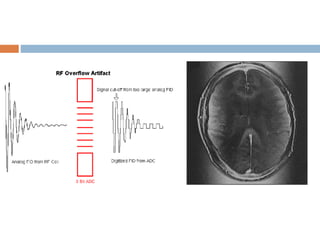

RF overflow/Shading artifact

 Non uniform, washed out appearance in an

image.

 Occurs when the signal received from the patient

is too intense to be digitized by analog to digital

converter.

 Auto prescanning usually adjusts the receiver

gain.

 Post processing methods also existing but may

be time consuming.

RF overflow/Shading artifact Non uniform, washed out appearance in an image.  Occurs when the signal received from the patient is too intense to be digitized by analog to digital converter.  Auto prescanning usually adjusts the receiver gain.  Post processing methods also existing but may be time consuming.